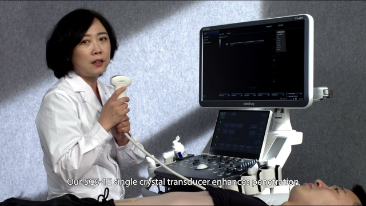

Od czasu kiedy zosta?a za?o?ona, Firma Mindray nieustannie poszukuje nowych sposob├│w na polepszenie precyzji w diagnostyce. Dzi?ki zastosowaniu najbardziej rewolucyjnej technologii ZONE Sonography? Technology, platforma ZST+ zastosowana w aparacie Resona 7 przenosi jako?? obrazu ultrasonograficznego na wy?szy poziom dzi?ki strefowemu uzyskiwaniu obrazu - zone acquisition i obr├│bkce danych kana?owych.

Oprócz uzyskiwania jako?ci obrazu typowego dla aparatów klasy premium, Resona 7 rozszerza mo?liwo?ci klinicznych badań USG dzi?ki rewolucyjnej funkcji V Flow, s?u??cej do oceny hemodynamiki naczyń, a tak?e najlepszej na rynku funkcji inteligentnego, automatycznego uzyskiwania p?aszczyzny na podstawie zestawów danych obj?to?ciowych 3D, umo?liwiaj?cej diagnozowanie stanu Centralnego Uk?adu Nerwowego u p?odu. Aparat Resona 7 ??czy w sobie najbardziej intuicyjn?, wielodotykow? obs?ug? za pomoc? gestów oraz wszystkie kluczowe funkcje kliniczne, co sprawia i? jest prawdziwym liderem we wprowadzaniu innowacji w ultrasonografii.